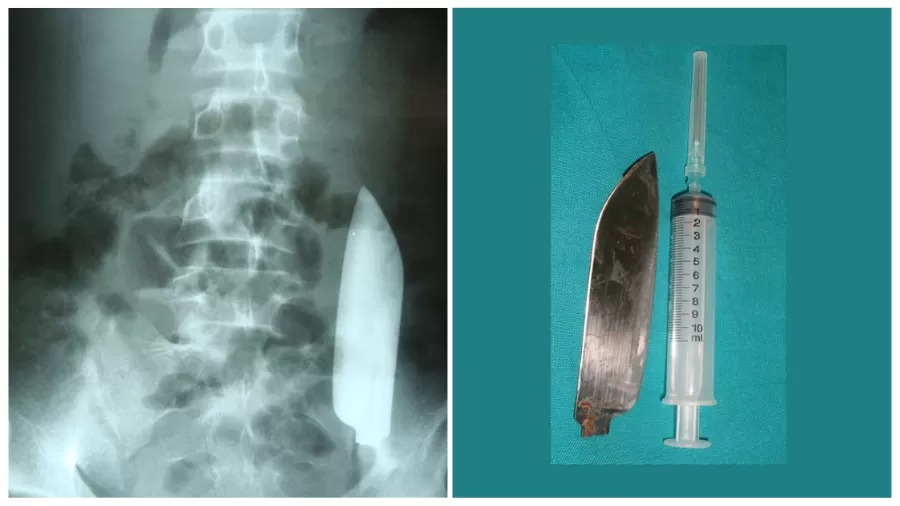

No dia seguinte, o jovem começou a sentir dores no abdômen. Ele foi ao pronto-socorro, onde os médicos fizeram uma radiografia e descobriram a lâmina dentro dele, que por sorte não perfurou nenhum órgão.

Os médicos removeram a lâmina cirurgicamente e o jovem se recuperou totalmente. Ele recebeu alta do hospital cinco dias depois.